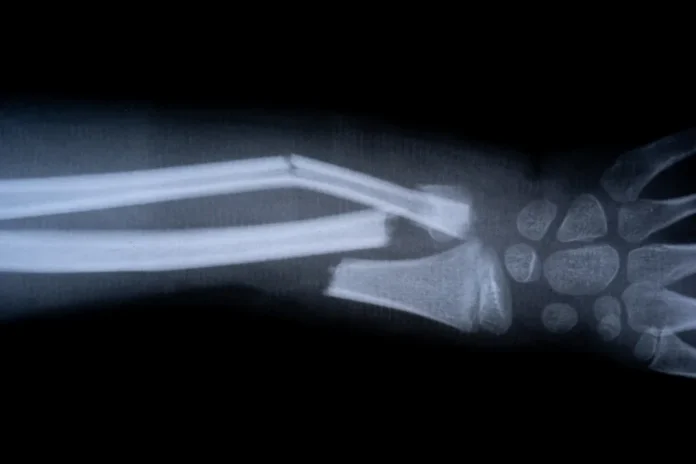

In one clinical trial, a patient with a wrist fracture was treated through a small incision. Instead of undergoing surgery with implants, the bone was repaired almost instantly. Three months later, follow-up examinations confirmed complete healing with no complications.